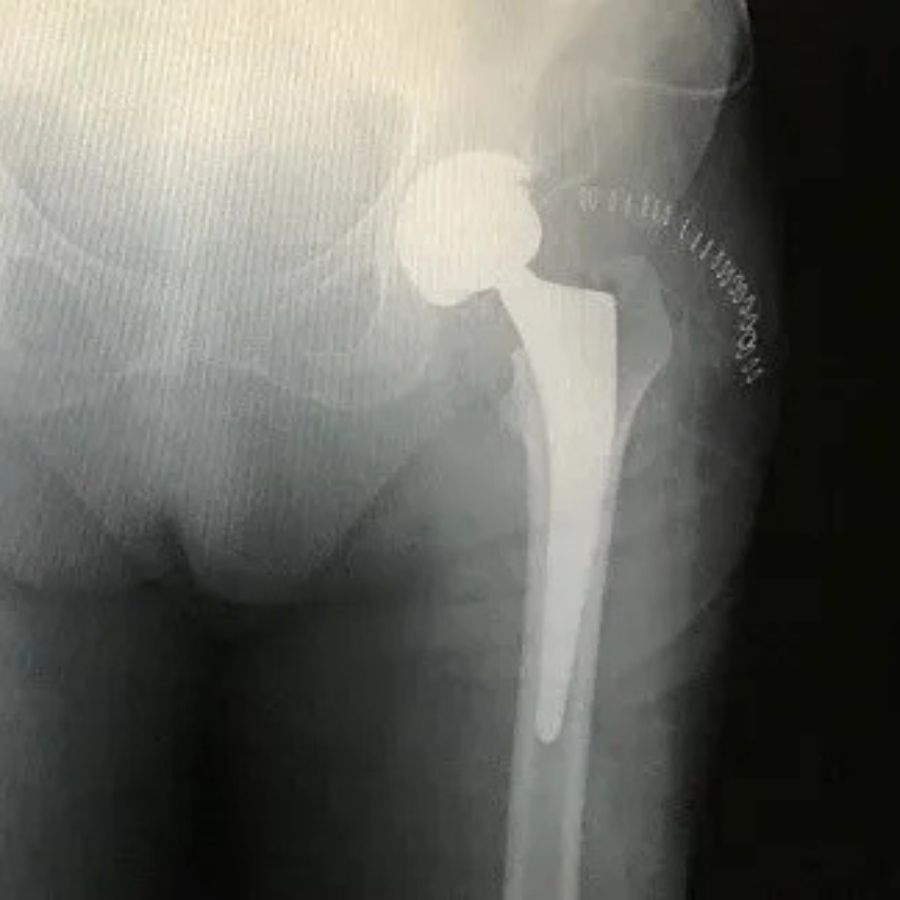

È un esperto nella Chirurgia Protesica del ginocchio e dell’anca, nelle tecniche di Artroscopia del Ginocchio, nella ricostruzione del legamento crociato anteriore e nelle plastiche di rinforzo esterne per le instabilità rotazionali del ginocchio. Altri interventi da lui eseguiti con frequenza sono il trattamento chirurgico delle fratture del piatto tibiale e del femore, trattamenti chirurgici per la lussazione della rotula. Tra i suoi campi d’interesse ci sono anche la Chirurgia Mini-Invasiva e la Traumatologia Sportiva. Da qualche anno è interessato all’applicazione di PRP per il trattamento di malattie acute e croniche dei tendini e delle articolazioni. Attualmente è Chirurgo Ortopedico presso la Clinica Fornaca di Sessant, Dirigente Medico di I livello presso l’Ospedale Humanitas Gradenigo e svolge la libera professione presso il suo studio privato a Torino.

Pubblicato su Francesco Porporato27 Luglio 2024Trustindex verifica che la fonte originale della recensione sia Google. Sono stato recentemente operato dal Dr. Surace per una protesi monocompartimentale al ginocchio e sono contentissimo dei risultati. Il Dr. Surace è un medico del tutto speciale: molto competente e attento nella valutazione del caso, sa essere nel contempo simpaticamente accogliente e rassicurante infondendo così tranquillità e fiducia anche nel paziente più timoroso. Grazie Dr. Surace! Francesco PorporatoPubblicato su cristiana bertero17 Giugno 2024Trustindex verifica che la fonte originale della recensione sia Google. Medico competente e molto disponibile con il paziente, sia nella fase pre-post operatoria.Pubblicato su Fabio Pignatelli16 Giugno 2024Trustindex verifica che la fonte originale della recensione sia Google. Medico molto competente e simpatico, effettuate due operazioni al ginocchio, recuperati in entrambi casi la completa mobilità in poco tempo dopo aver effettuato riabilitazionePubblicato su Consolata Boeri Bona15 Giugno 2024Trustindex verifica che la fonte originale della recensione sia Google. Tre settimane fa sono stata operata dal Dottore che ha eseguito un osteotomia secondo Fulkerson alla rotula e una meniscectomia mediale e laterale. L'operazione è andata ottimamente, lui è un ottimo professionista, attento ed empatico ho lasciato le stampelle dopo 3 giorni e appoggiato e caricato subito e dopo 3 settimane sono già in grado di camminare e fare la fisioterapia 3 volte a settimana. Lo consiglio vivamente. Un grazie di cuore anche all'equipe che mi ha operato, in particolare all'anestesista, la dottoressa Giulia Appendino, anche lei attenta e precisa!Pubblicato su Sorin Ionut Necula15 Novembre 2023Trustindex verifica che la fonte originale della recensione sia Google. A settembre sono stata operata di protesi monocompartimentale ginocchio e sono tornata ad avere una vita normale con un recupero molto rapido grazie al DOTTOR SURACE, ECCELLENTE CHIRURGO ORTOPEDICO e anche una bella persona da tutti i punti di vista.Grazie di cuore! Ringrazio anche alla sua segretaria, Daniela, molto attenta, gentile e disponibile, a tutta l'equipe della sala operatoria (impeccabile anche l'anestesista!), al personale del reparto e non per ultimo ai fisioterapisti. Grazie infinite! Lidia Elena N.Pubblicato su Mark Bianco18 Marzo 2023Trustindex verifica che la fonte originale della recensione sia Google. Chirurgo di qualità. Approccio diretto allo scopo senza tanti giri di parole. Protesi anca. il giorno dopo camminavo. Una ricchezza per ogni paziente che ne ha bisogno